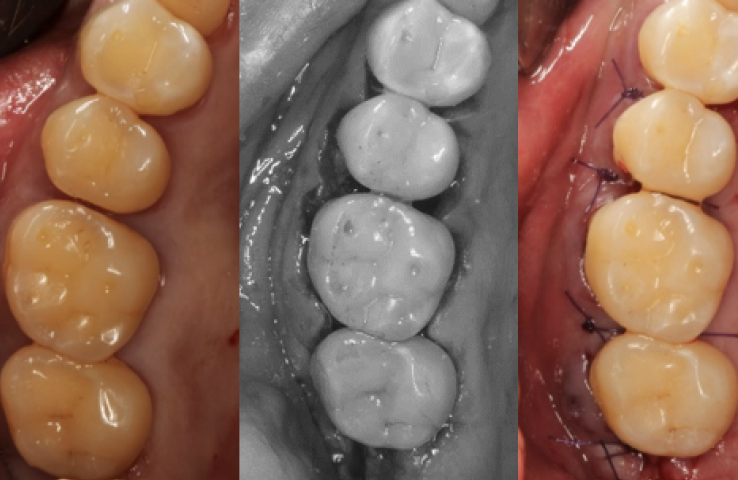

잇몸수술

치주염이 심하게 진행된 경우 잇몸절개를 통해 깊숙히 있는 염증까지 깨끗이 제거하고 봉합합니다.